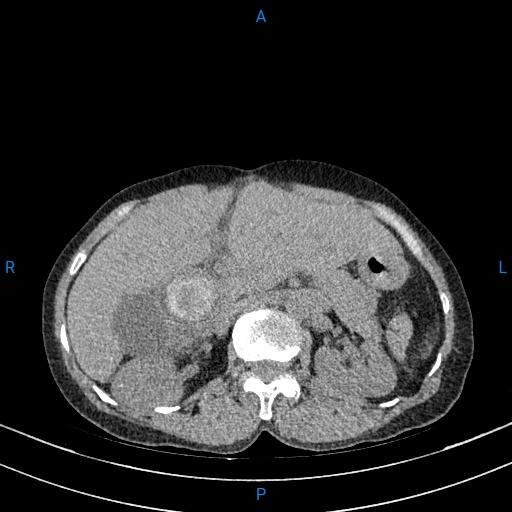

Vừa qua, các Bác sĩ Bệnh viện Đa khoa Hải Dương đã thực hiện phẫu thuật cho một trường hợp bệnh nhân Trương Thị T. (62 tuổi) ở Hòa Bình, Xã Thanh Miện, Thành phố Hải Phòng có tiền sử mổ sỏi mật 3 lần. Gần đây, Bệnh nhân ở nhà mệt mỏi, ăn uống kém, đau âm ỉ vùng thượng vị và hạ sườn phải, vàng da, củng mạc vàng nên đến viện kiểm tra. Qua thăm khám và chụp cắt lớp vi tính, các Bác sĩ thấy đường mật trong ngoài gan giãn nhiều, ống mật chủ giãn 27mm có nhiều sỏi, sỏi lớn nhất kích thước 38x 31mm, sỏi lớn đường mật gan phải kích thước 22x17mm, sỏi lớn đường mật gan trái 26x15mm. Bệnh nhân được chẩn đoán nhiễm trùng đường mật do sỏi. Hội chẩn đánh giá bệnh nhân có sỏi ống mật chủ to, nhiều sỏi đường mật trong gan, chỉ định phẫu thuật mở ống mật chủ lấy sỏi và nội soi đường mật trong mổ ống mềm kết hợp tán laser sỏi đường mật trong gan.

Hình chụp cắt lớp vi tính sỏi ống mật chủ của bệnh nhân T.